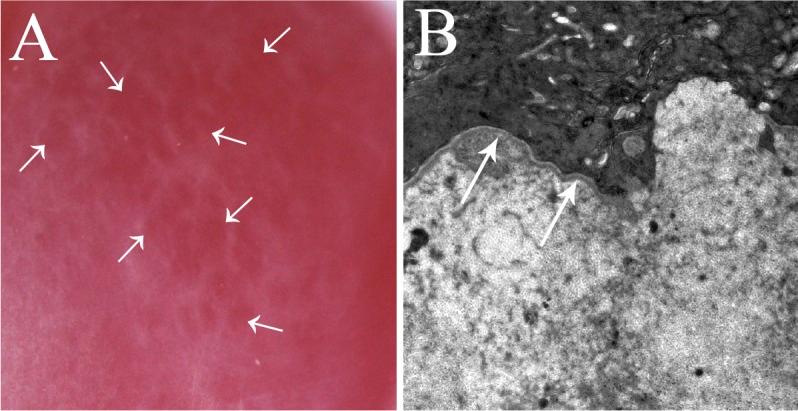

The epithelium and epithelial basement membrane (EBM) and/or endothelium and Descemet's basement membrane (BM) are commonly disrupted after corneal injuries, surgeries, and infections. Regeneration of these critical regulatory structures relies on the coordinated production of BM components, including laminins, nidogens, perlecan, and collagen type IV by epithelial, endothelial, and keratocyte cells. Whether a cornea, or an area in the cornea, heals with transparency or fibrosis may be determined by whether there is injury to one or both corneal basement membranes (EBM and/or Descemet's BM) and delayed or defective regeneration or replacement of the BM. These opaque myofibroblasts, and the disordered extracellular matrix these cells produce, persist in the stroma until the EBM and/or Descemet's BM is regenerated or replaced.

Corneal stromal fibrosis (also termed "stromal scarring" or "late haze") occurs as a consequence of BM injury and defective regeneration in both the anterior (EBM) and posterior (Descemet's BM) cornea. The resolution of fibrosis and return of stromal transparency depends on reestablished BM structure and function. It is hypothesized that defective regeneration of the EBM or Descemet's BM allows key profibrotic growth factors, including transforming growth factor beta-1 (TGF-β1) and TGF-β2, to penetrate the stroma at sustained levels necessary to drive the development and maintenance of mature opacity-producing myofibroblasts from myofibroblast precursors cells, and studies suggest that perlecan and collagen type IV are the critical components in EBM and Descemet's BM that bind TGF-β1, TGF-β2, platelet-derived growth factor, and possibly other growth factors, and regulate their bioavailability and function during homeostasis and corneal wound healing.